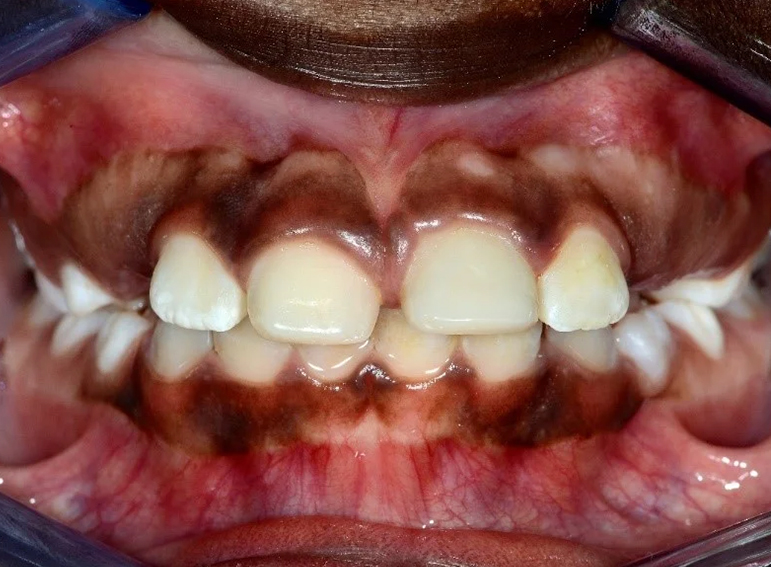

Hypoplastic primary molars: Placement of hall crowns, extraction of URD and ULD, composite restorations of LRD, LLD and…